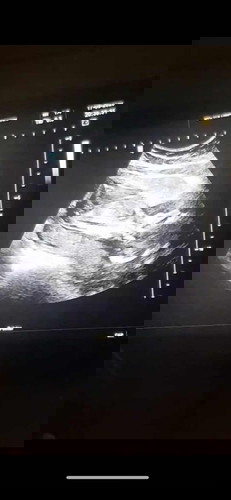

บี๋เอาหัวไปซุกในที่แคบ17week

หลังจากตรวจNiftyไปเดือนที่แล้วโคโมโซมนู๋ปกติค่ะ เพศหญิง วันนี้17.9.20 หมอนัดซาวดูบี๋อีกครั้งและฉีดวัคซีนไข้หวัดใหญ่ค่ะ นู๋ขี้อายไม่ให้เห็นหน้าเลยค่ะ เอาหัวลงไปมุดกับรก บังหน้ามิดเลย คุณหมอเลยตรวจปากไม่ได้เลยลูก นู๋ตัวยาว184เซนแล้ว นน.หมอไม่ได้บอกค่ะ